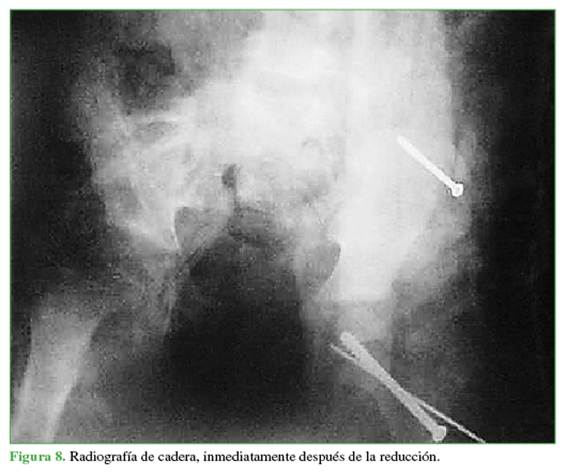

Mediante la técnica de Parsch3 por abordaje mínimo de Hueter,4 se redujo el desplazamiento de la cabeza femoral, y se colocaron un tornillo y una clavija por un abordaje lateral mínimo bajo intensificador de imágenes.

Ya drenada y estabilizada la cadera, se colocó otro tornillo canulado, por vía percutánea, para estabilizar el gran fragmento desprendido del ala ilíaca, y se inmovilizó al paciente con un yeso pelvicalzón para la apertura en libro y, mediante tracción de partes blandas, se colocó luego al paciente en tracción posquirúrgica. Cumplió 3 semanas de tracción y se logró la reducción anatómica de las fracturas (Figuras 6-8).